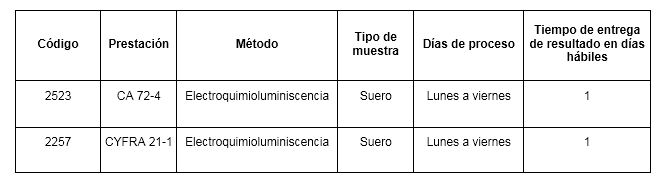

Pase para saber Psicológico pueblo Marcadores tumorales en el diagnóstico de cáncer epitelial de ovario: caso de estudio Tumor markers in the diagnosis of epit